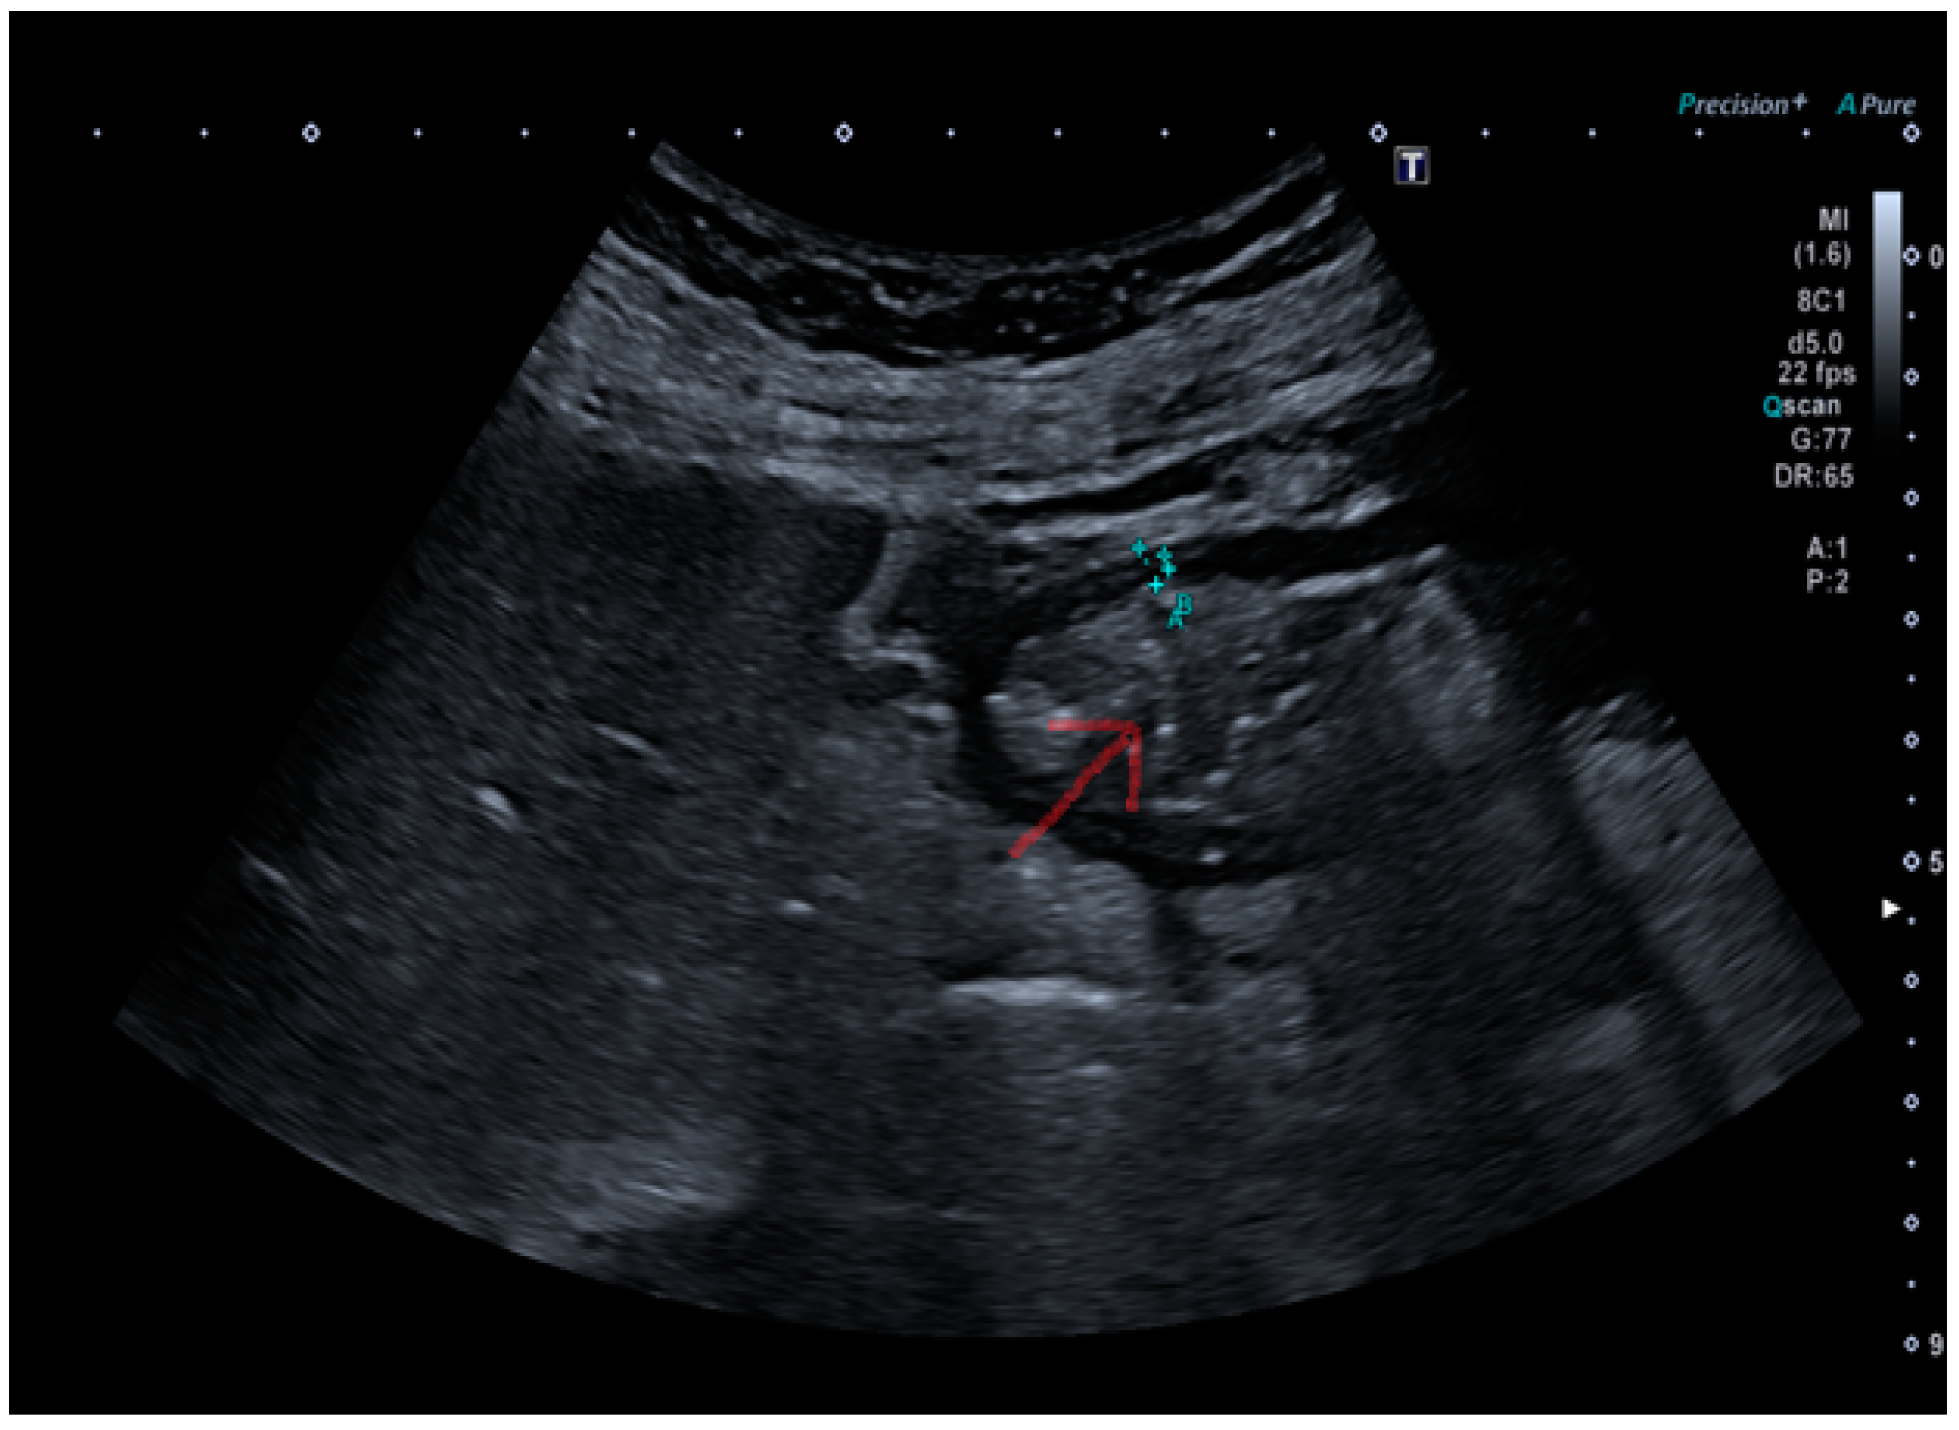

The submucosal thickness and reduced motility were significantly higher in the group of patients with histological confirmation of Helicobacter pylori-related gastritis (p < 0.001) (Figure 1 and Figure 2a,b).

Figure 1. Stomach explored by convex probe containing food ingests in Helicobacter pylori-positive patient. The red arrow in the image indicates the presence of ingested material in the stomach.